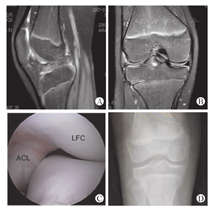

盘状半月板损伤常见的症状包括疼痛、关节弹响、关节交锁、股四头肌萎缩等,虽然并不具备特异性,但是对诊断有提示性,最终确诊还要结合影像学检查[10,11]。DLM在X线片上经常表现为外侧关节间隙变宽、股骨髁平坦及胫骨髁间棘发育不良等,但特异性不高。目前,诊断DLM最常用的影像学检查为磁共振成像,其中最准确的诊断方法是在冠状位上半月板的最小直径超过外侧胫骨平台的20%,以及在矢状位上前后角直径之和超过半月板最大直径的75%,这两种方法的敏感性及特异性均超过95%[12](图2)。